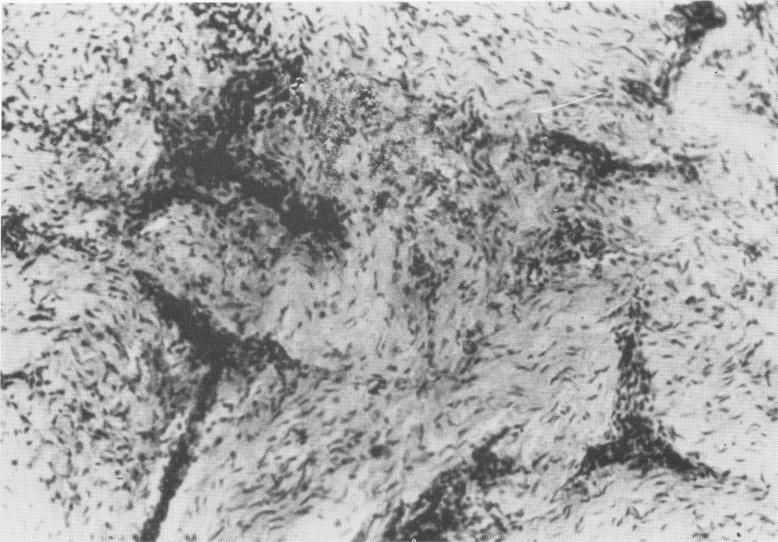

Fig. 4-13. Fibrocytic connective tissues from around a Formiggini type implant inserted by Perron-Andres. (From Chercheve, R.: Les implants endo-osseux, Paris, 1962, Librairie Maloine.)

2 Fibrocytic connective tissues around endosseous Formiggini type implant